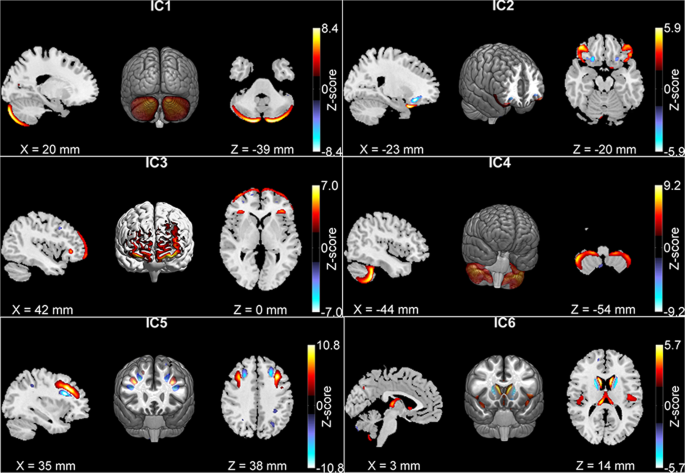

In the previous study we have reported five GM components in adults significantly associated with working memory, inattention, or diagnosis. The analyses and results of our previous study are summarized in the supplementary text. The five components are plotted in Fig. 1 (Independent Component (IC) 1–5). Using the homogenous subgroup 427 participants’ GM data, a separate ICA extracted highly similar components. The correlations between subgroup components and full-sample components were 0.97, 0.85, 0.95, 0.96, and 0.97 for the five components, respectively. The correlations between loading coefficients of the components were 0.98, 0.96, 0.99, 0.98, and 0.98. The validity of the five components has been provided before24. Additionally, we tested possible confounding effects from three MRI quality metrics (coefficient of joint variation, contrast-to-noise ratio, entropy focus criterion), using two regression models: (1) working memory or symptom = GM loading + age + gender + family (random effect) + three MRI quality metrics, and (2) GM loading = case/control + family + three MRI quality metrics. The new test results agreed with previously reported association results (components were significantly associated with working memory, inhibition or case-control status with p < 0.003). Given the high consistency, we continued our analyses with the full-sample derived components previously reported.

Across adults and adolescents, three GM components (ICs 2–4 in Table 2A) showed consistent associations with either working memory or inattention. Component 2, the inferior frontal gyrus, and Component 3, the superior and middle frontal gyri, were positively associated with working memory in both adults and adolescents. More GM volume was associated with higher (better) working memory scores in all participants. Component 4, the cerebellar tonsil and culmen, was negatively associated with inattentive symptom in both adults and adolescents, where lower GM volume was associated with higher (worse) inattentive score. The effect size was computed as the percentage of variance explained, R-square, listed in Table 2. In general, the variance explained by each GM component is small (around 2%), but significant. In addition to these significant associations, it is noteworthy that adolescent patients showed nominal GM reduction in four of the five components (p < 0.05), while adult patients showed GM reduction in two components (one passed FDR and one had p < 0.05).

Twenty components were extracted from the adolescent data of which twelve were highly similar to those in adults (r ≥ 0.5, see Supplementary Table 1). Two components (Fig. 2) showed significant GM reduction in patients and were also significantly associated with inattention or working memory in adolescents. For these two components, medicated cases had increased GM volumes compared to unmedicated cases (p = 4.64 × 10−3 and p = 3.95 × 10−2, respectively). After projection to adults, no medication effects were observed. Thus, medication effect was controlled only for adolescents. As shown in Fig. 2, Component A comprised left hemisphere, cerebellar tonsil and culmen, lingual gyrus, and cuneus. Component B comprised bilateral insula, inferior frontal, superior temporal gyri, and caudate nucleus. Table 2B lists out associations of the two components with working memory, inattention, and diagnosis in both age groups. GM volume of Component A was negatively associated with inattentive symptom in adolescents and adults and showed a significant reduction in adolescents with ADHD. GM volume of Component B was positively associated with working memory in both groups and showed a significant reduction in adolescents with ADHD. The effect sizes, R-squares, are listed in Table 2B. No significant comorbidity effect was observed for the components in both groups.

Literatures have shown that subcortical regions like the caudate nucleus and putamen were significantly reduced in ADHD patients and the reduction seemed to diminish over time from childhood to adulthood25,38,53. Functionally fronto-striatal network54 is a key component supporting executive function including attention and working memory55, and its alterations in ADHD34,56 is hypothesized as a core of one ADHD etiology model6. Given the relevance, we specifically picked components including the caudate nucleus: one adult component, (Component 6 in Fig. 1, comprising caudate nucleus, superior temporal and insula), and one adolescent component (Component B in Fig. 2). These two components were highly correlated (r = 0.58, p < 1e-16). But the adolescent component had more areas in insula and inferior frontal gyrus and less in the caudate nucleus relative to the adult one. As listed in Table 2A, Row IC 6 and Table 2B, Row IC-B, the adult component showed no associations in adults but nominal associations with working memory and diagnosis in adolescents (p < 0.05), while the adolescent Component B showed consistent significant associations with working memory in both groups and significant GM reduction in adolescents.